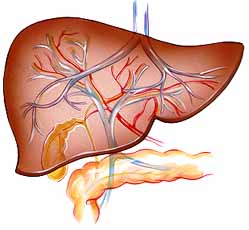

Liver